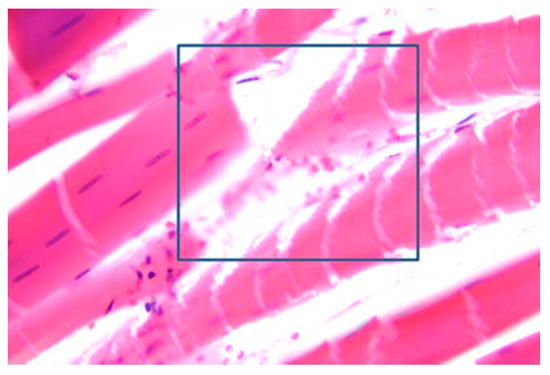

3.5. Muscles Damage

| DeBono, et al. [36] | HV | Muscle fiber fragmentation; red blood cell extravasation; neural damage; |